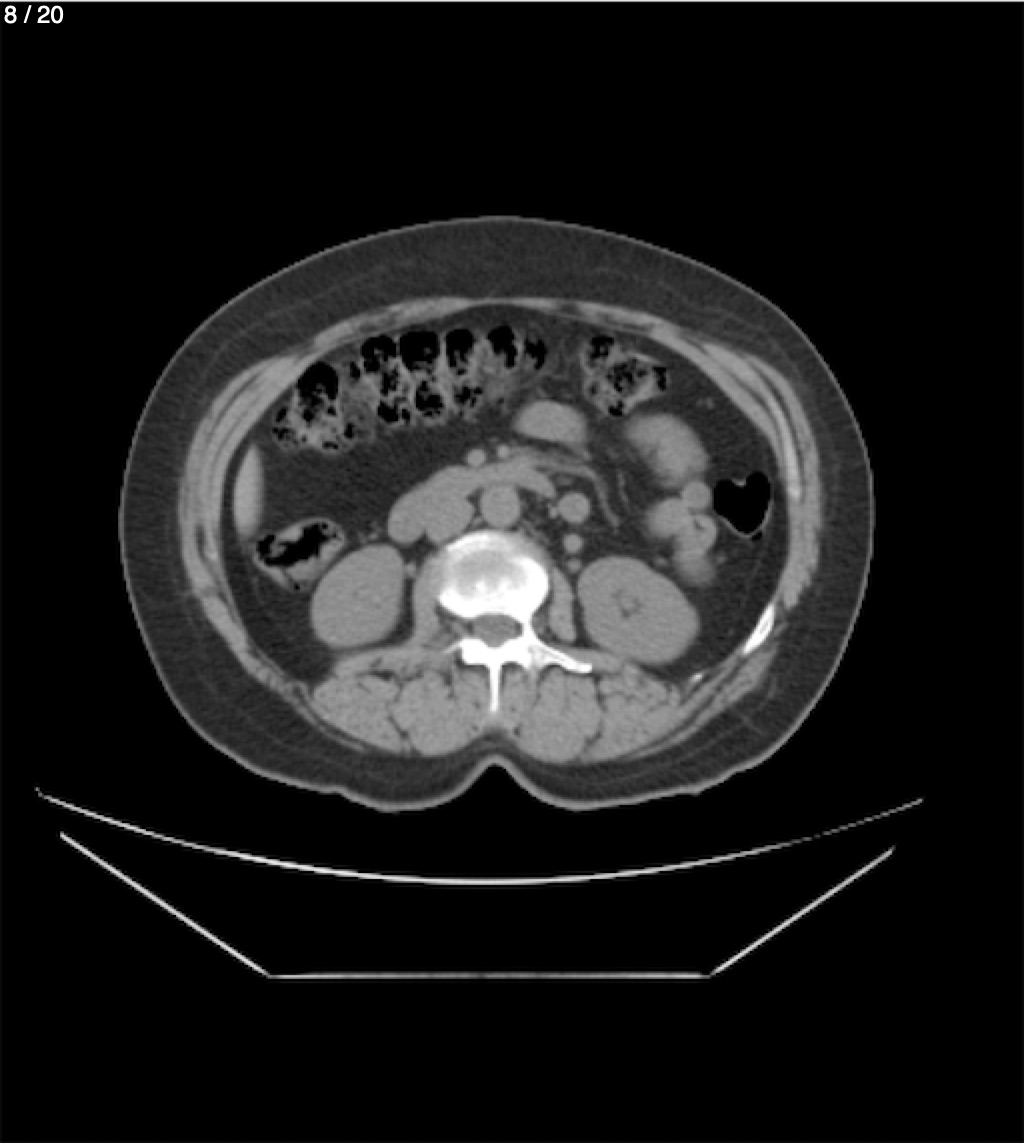

Maria Enrique Giron Dominguez63A - T.C Abdomen Simple